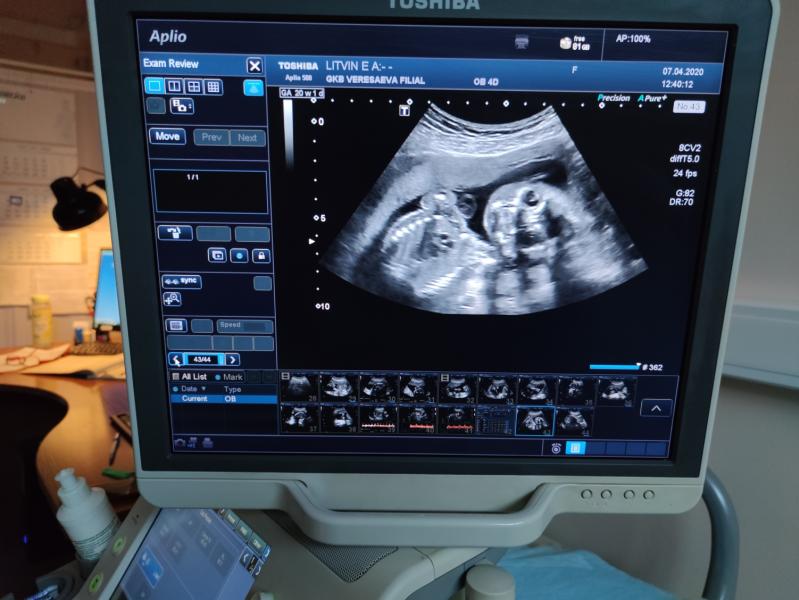

Второй скрининг пройден!!!

У нас будет девочка 🤪

Длинногая девочка, все у нее там хорошо ( на одну неделю опережает), а вот у меня не очень